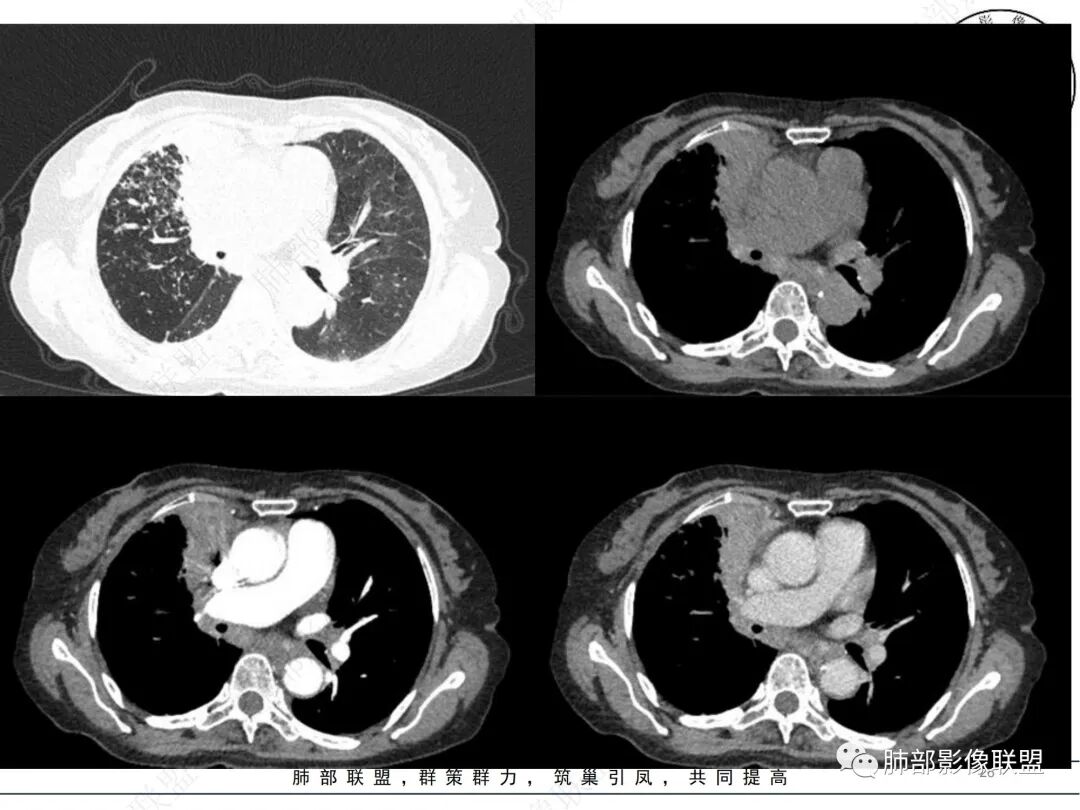

2. CT示右肺上叶多发斑片状实变影,结节影,集群散落,夹杂条索影,边界可分辨,有沿支气管血管束分布趋势,可见树芽征。病灶新旧不等、密度不均。右上叶支气管壁不均匀节段性增厚狹窄,斑点状钙化。纵隔旁部分肺组织含气不良,并显示轻度扩张支气管。病灶邻近胸膜增厚,轻度强化。

4.纵隔多发增大淋巴结,部分融合、钙化。

成簇分布斑片影、结节影、树芽征,边界较清楚,新旧不等,节段性支气管壁增厚伴钙化,管腔狭窄,纵隔及肺门淋巴结增大钙化等都较符合“继发性肺结核、支气管内膜结核”诊断。

继发性肺结核尾随而来的淀粉样变性应当想到,但支气管肺组织淀粉样变性受累及分布范围应当更加广泛、更加弥漫。

老年女性患者应当警惕基础疾病办法新生物的可能性,如常见的肺腺癌等,须仔细甄别有无密度相对均匀的分叶状的磨玻璃或实性密度结节影,以及其他与众不同强化病灶,尤其应当重视复查对比。